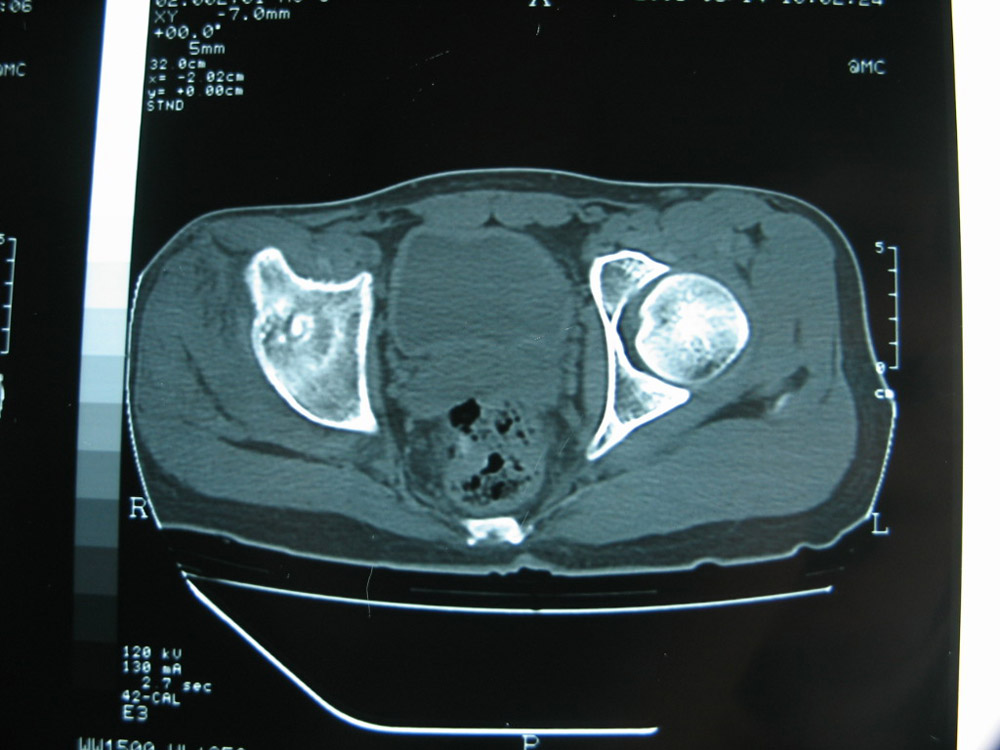

以下是引用卜一在2007-1-25 16:33:00的发言:[br]右侧髋关节股骨头及髋臼骨骨小梁疏松 粗糟,股骨头外形毛糟,软组织似肿胀,间隙略变窄.考虑:1 髋关节结核可能性大.2 缺血性坏死?3 化脓性髋关节炎?

以下是引用hhcckk在2007-1-25 17:18:00的发言:[br][br]支持髋关节结核,[br]依据关节面破坏,有脓肿,脓腔内有钙化,关节周围增生不明显,鉴别[br]1化脓性的病变增生明显,临床上有高热[br]2创伤引起的关节炎,无菌坏死不会引起关节面的破坏,而且不会在这么短的时间内出现[br]